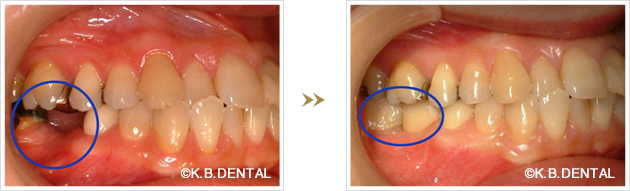

親知らずの移植症例

当院では、親知らずを他の場所の奥歯に移植するケースも数多く行っております。奥歯の移植治療を考えられている方は、一度ご相談ください。

下顎インプラント埋入と歯牙移植を同時に行なったケース